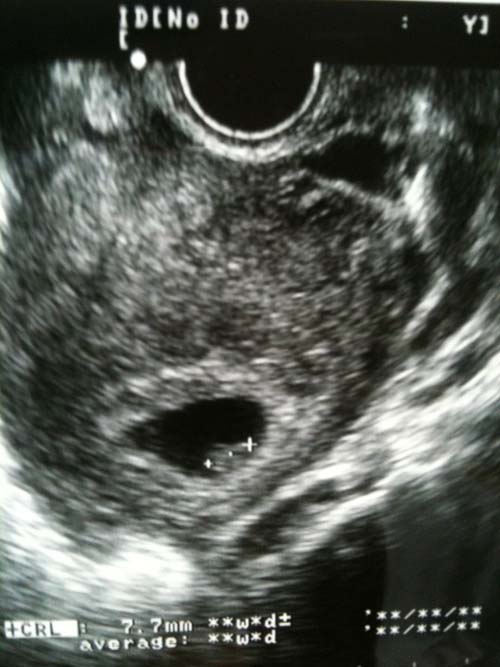

先日、妻の体調がおかしく、

病院にいったところ、

なんと

第二子が!!!!

まさかとは思っていましたが、

このタイミングはちょっと予測していませんでした。

去年息子が生まれたので、2歳違いの子供

できることになります。

子育ては大変ですが、

その分喜びも大きいと思います。

21世紀少年

がまた一人、生まれてきます。